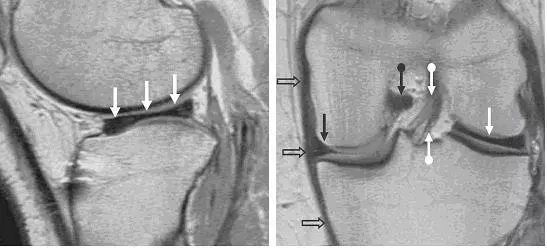

图 11 内侧半月板桶柄状撕裂——双后交叉韧带征

左图:经髁间切迹的矢状面,可见剥离开的低信号半月板块(白色箭头)平行于正常的后交叉韧带(黑色箭头)。右图:冠状面可见剥离的半月板块(白色直箭头),在正常的后交叉韧带(黑色箭头)下方。残留的半月板外缘(白色圆箭头)形态异常且比正常(对侧)的小。